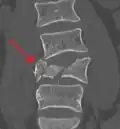

A burst fracture of L4 as seen on plane X ray -

A burst fracture of L4 as seen on CT -

A burst fracture of L4 as seen on CT